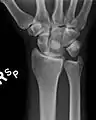

The lunate bone is the most frequently dislocated carpal bone.

Dislocated lunate